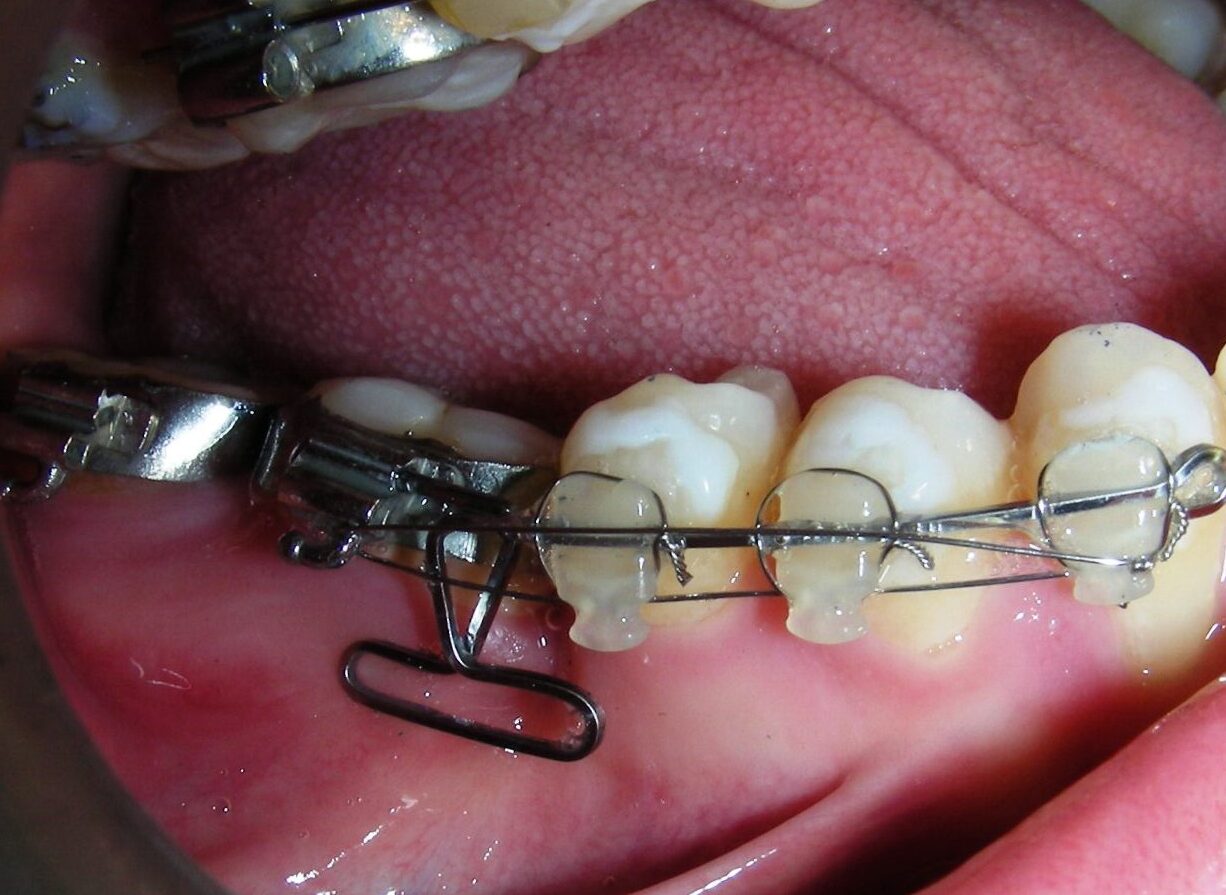

Having successfully achieved the expansion, we proceed to the intrusion of the posterior superior sectors, modifying the Hyrax by adding anchoring hooks at the buccal level of the first premolars. Using the Hyrax as anchorage, we sought a parallel intrusion. This could be replaced by a palatal bar. TADs were installed bilaterally at the mesial level of the first molars, inserting them as parallel as possible to the roots.

Simultaneously we begin with the alignment of the lower arch ,Simultaneously we began with the alignment of the lower arch with Roth prescription ceramic braces .022 . Henry Schein®

As the reader may infer, alignment and leveling of the upper anterior segment are being intentionally deferred at this stage of treatment. This strategic decision is based on the primary objective of closing the anterior open bite not through anterior extrusion, but by means of controlled posterior intrusion. This biomechanical approach promotes a counterclockwise rotation of the mandible, which leads to a increase in the facial axis angle and improvement in vertical facial proportions. By avoiding early anterior alignment, we prevent any premature vertical displacement of the upper incisors.

Clinical changes became evident after 12 months of treatment with posterior intrusion with TADs and nickel-titanium closed coil spring (NiTi), until subsequent follow-up appointments revealed no further significant changes. At that point, it was noted that the most distal molars remained in occlusal contact and had not followed the intrusive movement of their mesial neighbors.

The vertical vector of intrusion was located too far posteriorly to allow for the placement of TADs in that region. At this point, the utility arch developed by Dr. Ricketts was introduced into the mechanics . I referred to as the “Tilting Utility Arch.” made with Blue Elgiloy .017″ × .025″. It was employed as a lever arm to transmit the intrusive force generated by the coil spring and anchored by the TADs.

The upper brackets were bonded solely for the purpose of providing stability to the utility arch . Following the hierarchically structured treatment plan, we proceed with the alignment and leveling phase in order to enable mesialization of the posterior segments using sliding mechanics, which works effectively in conjunction with Roth prescription brackets .022.